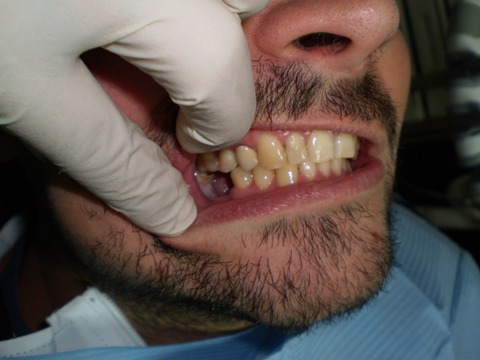

Ejemplo Implantes